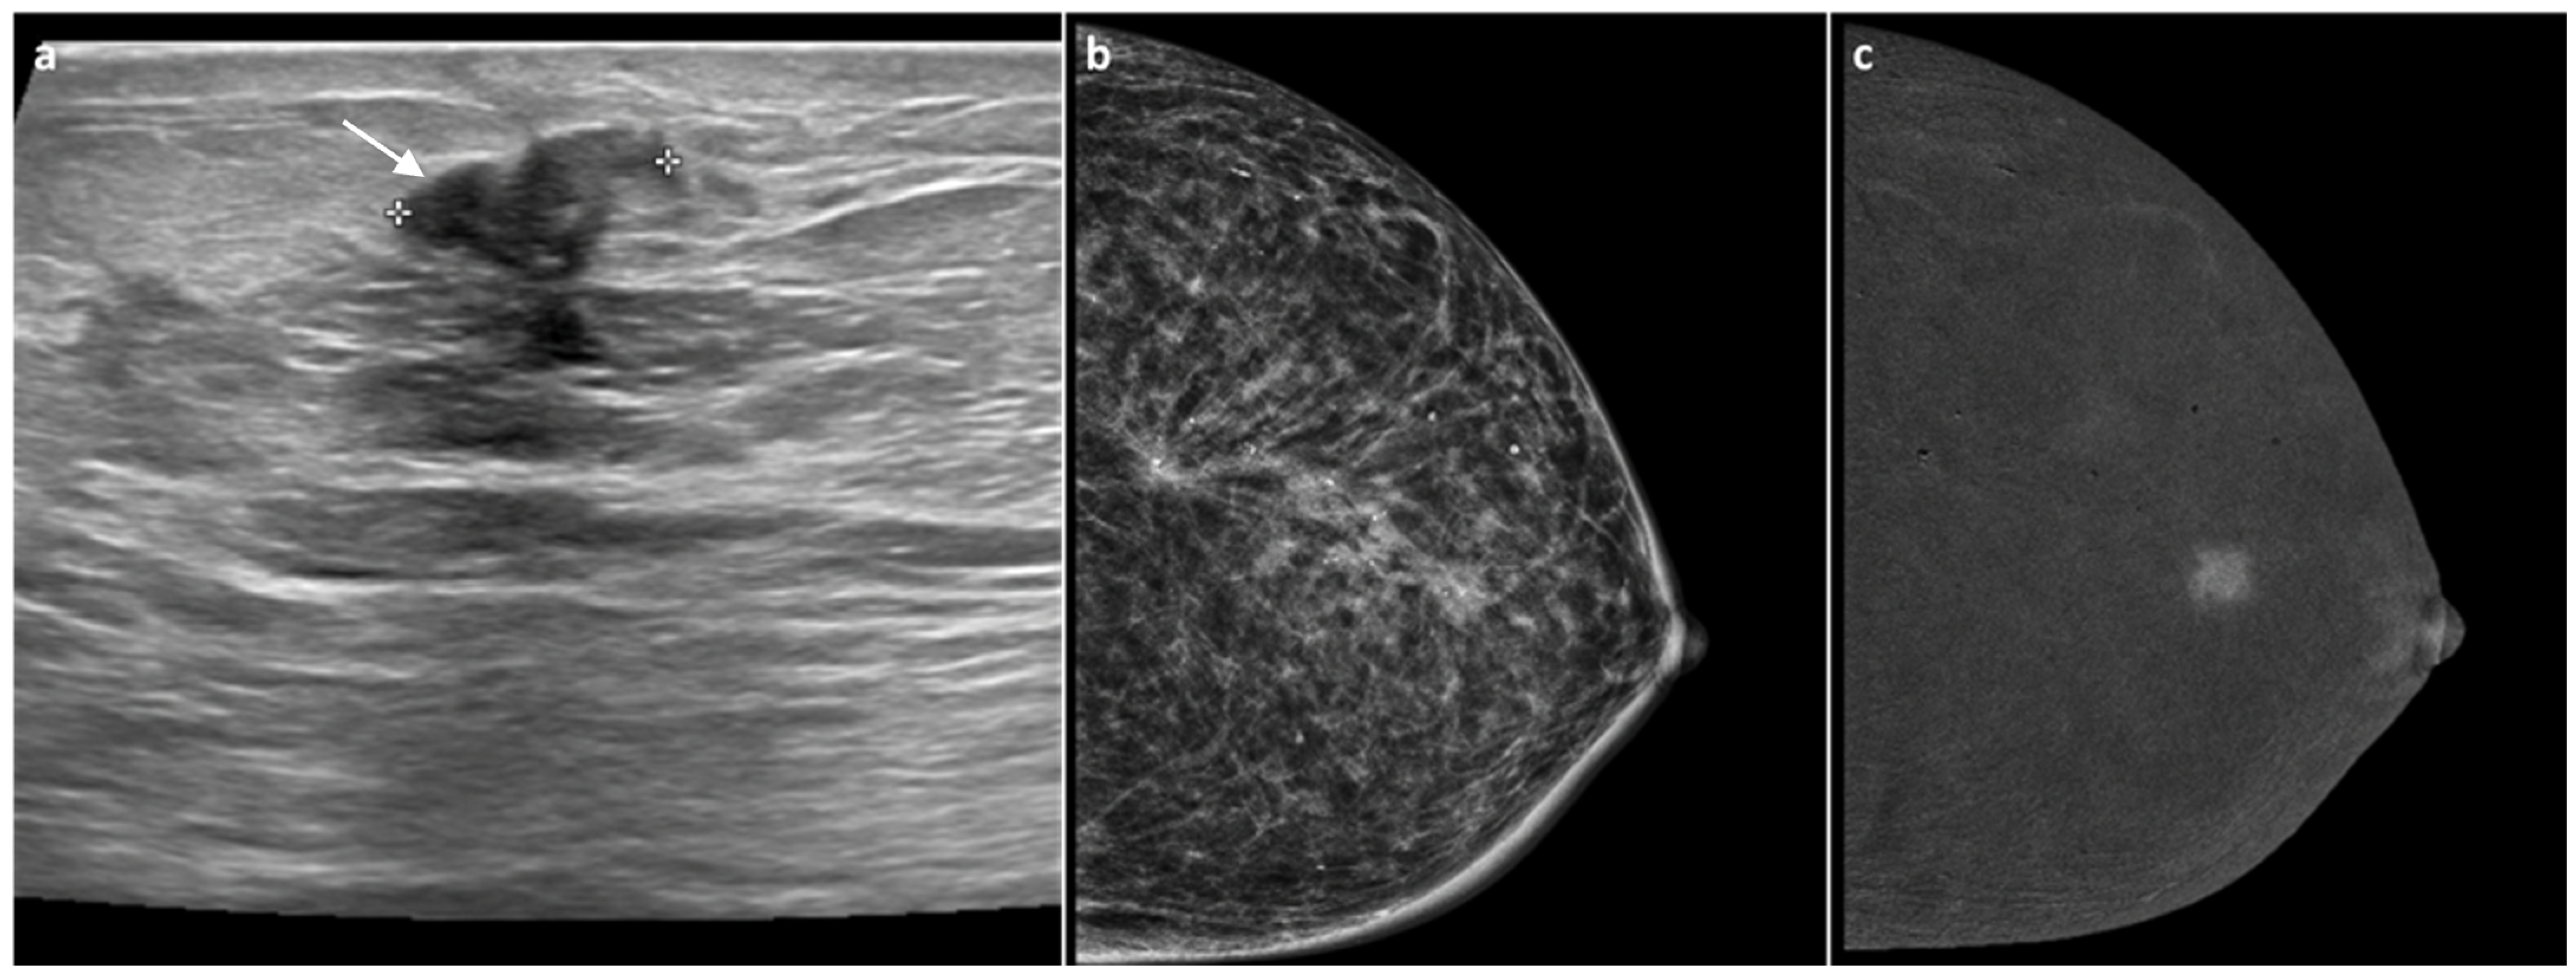

3.2. CEM Examination and Analysis